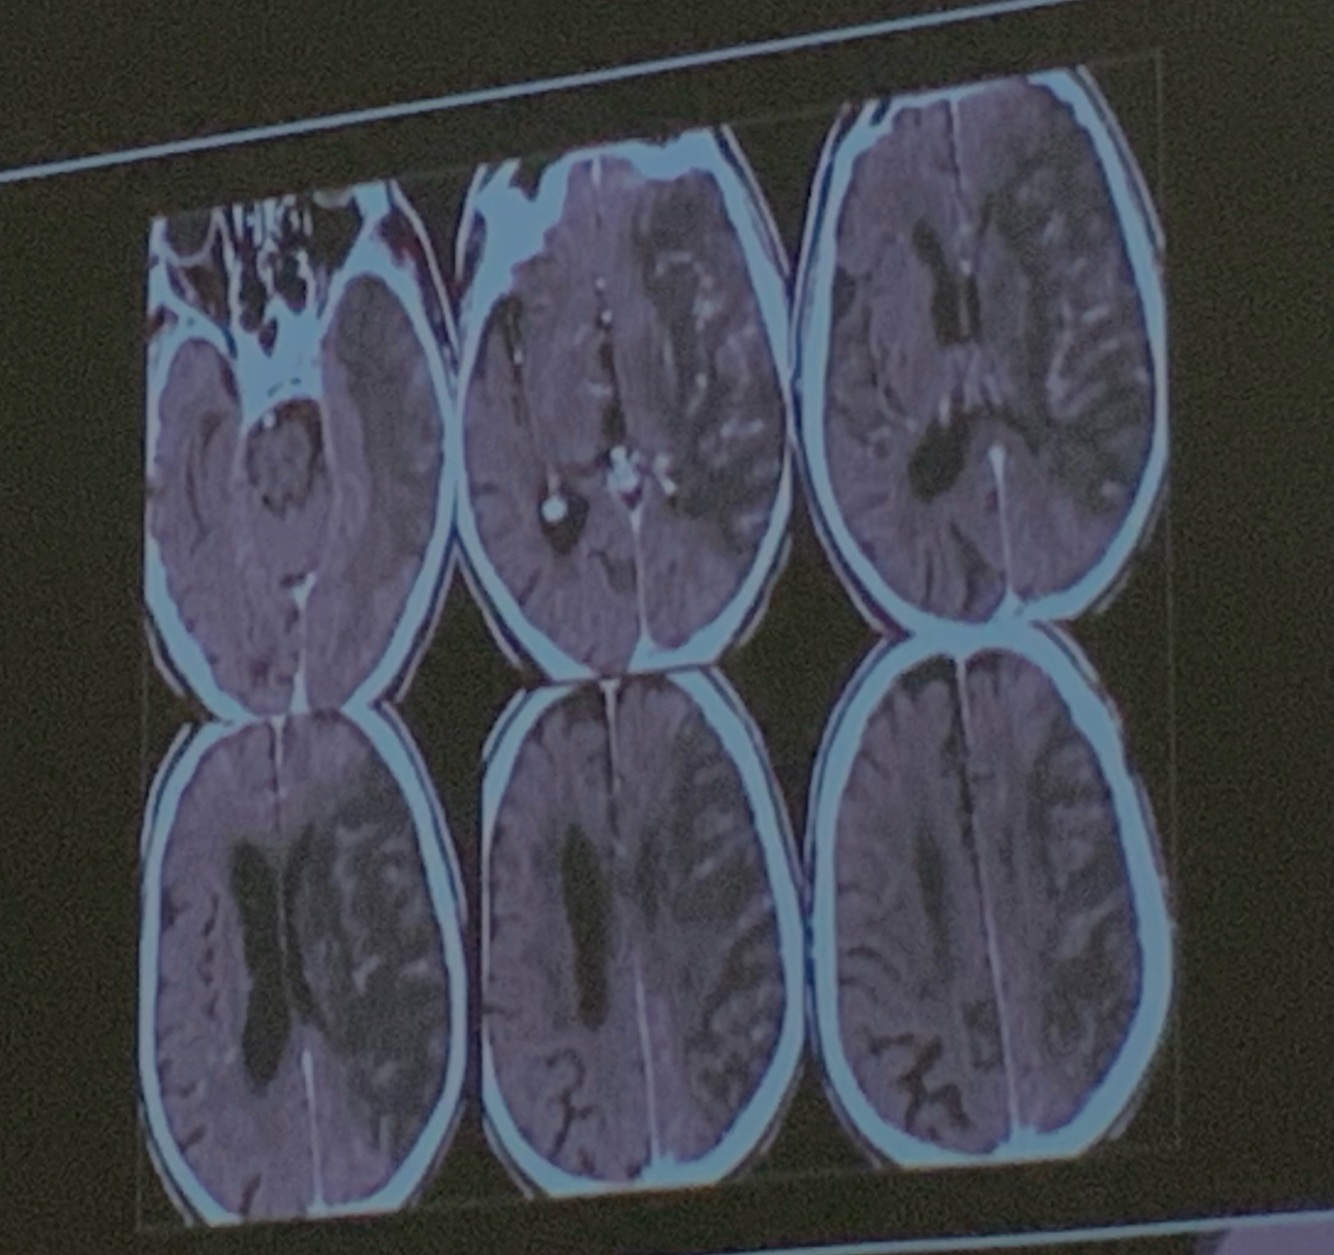

11

Q

Que arteria se encuentra afectada

A

ACA

How well did you know this?

1

Not at all

2